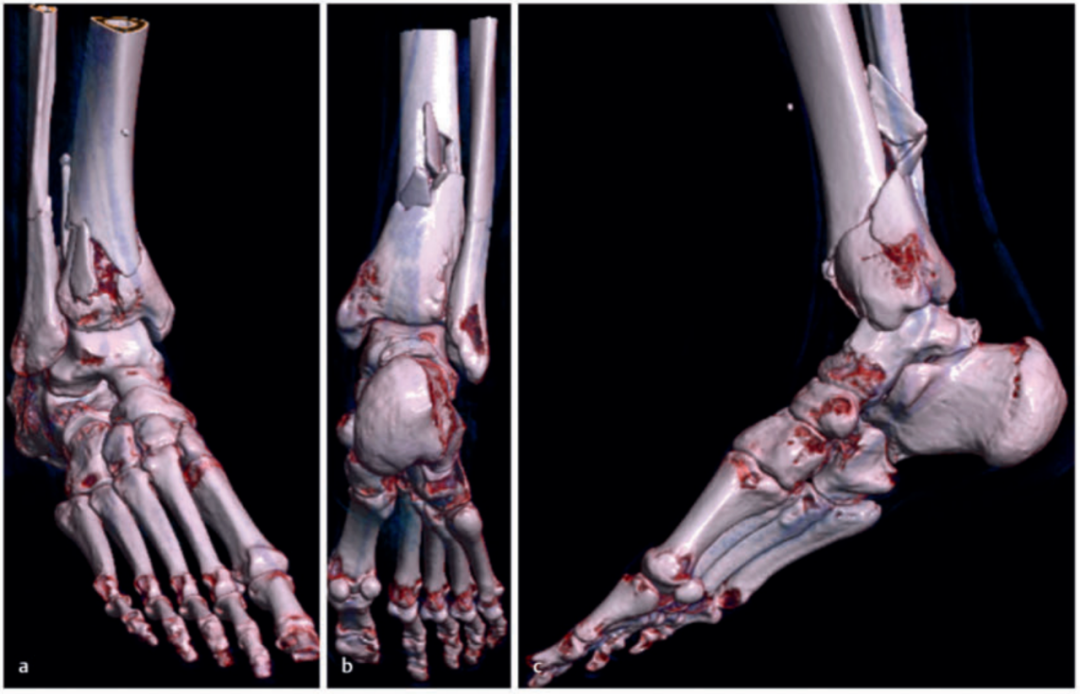

病例2受伤后入院首先植入跨踝关节外固定架,待软组织肿胀消退后,先对腓骨骨折进行微创固定,随后逐步完成复杂的胫骨Pilon骨折复位与固定。

术中临床图像显示了损伤的严重程度,同时体现了微创手术技术的优势,以及在必要时下胫腓联合切开复位重建的重要性。借助斯氏针的 “操纵杆(Joy-Stick)” 技术,可显著简化关节面的复位操作。